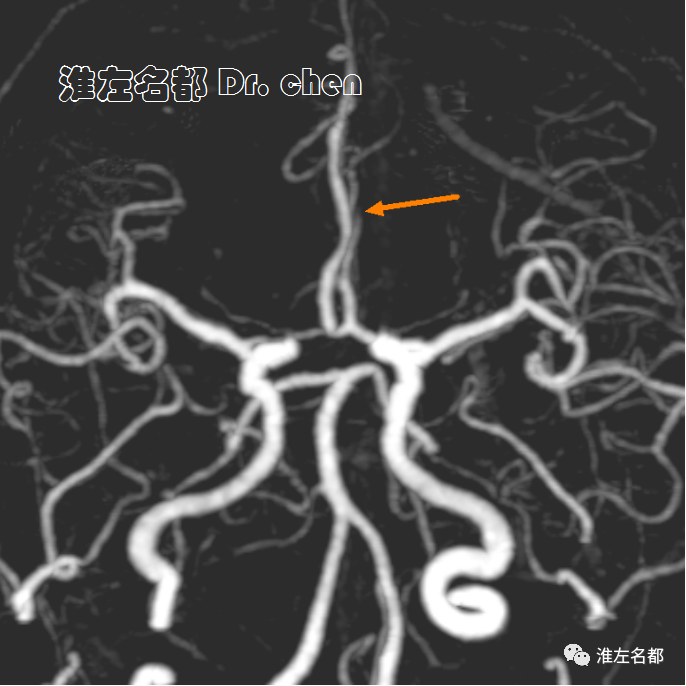

△头颅CTA:左侧大脑前动脉A2段远端闭塞(橙箭)。

△颈部CTA:左侧颈内动脉颅外段螺旋样延长迂曲(白箭)。